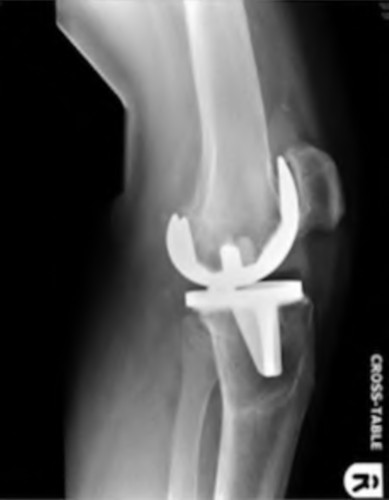

A 64-year-old woman with osteoarthritis underwent bilateral total knee replacement 3 years ago. Current radiographs are shown in Figure A. She reports a 3-month history of bilateral knee pain while at rest and increasing swelling in the knees. Her ESR and CRP are elevated and bilateral knee aspiration cultures reveal Staphylococcus aureus. What is the most likely outcome if the patient undergoes simultaneous, bilateral knee resection arthroplasty with cement spacer and a course of intravenous antibiotics?

This patient presents with bilateral total knee arthroplasty infection.

Wolff et al report Level 4 evidence of 18 patients followed an average of 5 years after bilateral TKA infection. Eleven patients were initially treated with attempts to salvage the original prosthesis (polyethylene l liner exchange, I&D, IV antibiotics and chronic oral suppressive antibiotics. With prosthesis retention, 9/11 (81%) developed recurrent infection at a mean of 15 months. The other 10 patients initially underwent resection arthroplasty with cement spacer and a course of IV antibiotics. Seven of the 10 (70%) underwent reimplantation at a mean of 3 months (6 weeks to 5 months) and none of the patients required revision at mean of two years follow up. Satisfaction rates were significantly higher among this group of patients. The authors advocate the protocol of bilateral TKA resection arthroplasty with cement antibiotic spacer and course of IV antibiotics followed by prosthesis reimplantation.